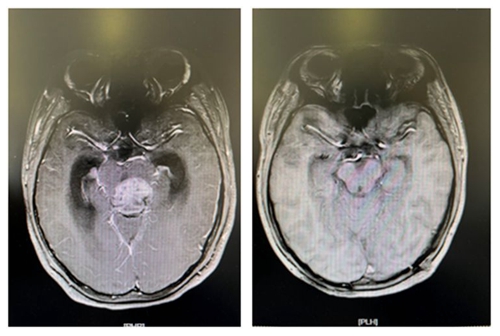

术前肿块影像                                                术后全切影像

今年40多岁的患者葛某是一位大货车司机,今年三月中旬在云南省驾驶货车途中突发剧烈头痛,致使左侧肢体瘫痪,言语不清。所幸及时送医,随后诊断为脑干区海绵状血管瘤并出血,手术风险难度极大,如再次出血则凶多吉少。几经周折,患者找到中南大学湘雅三医院神经外科王知非教授团队,王知非教授团队为其制定了详细周密的手术方案。3月30日,在全麻插管下为患者成功实施了右侧脑干丘脑血管畸形切除及血肿清除术。术后患者恢复良好,偏瘫言语不清等症状得到了明显改善,目前已出院前往康复医院继续后期康复。